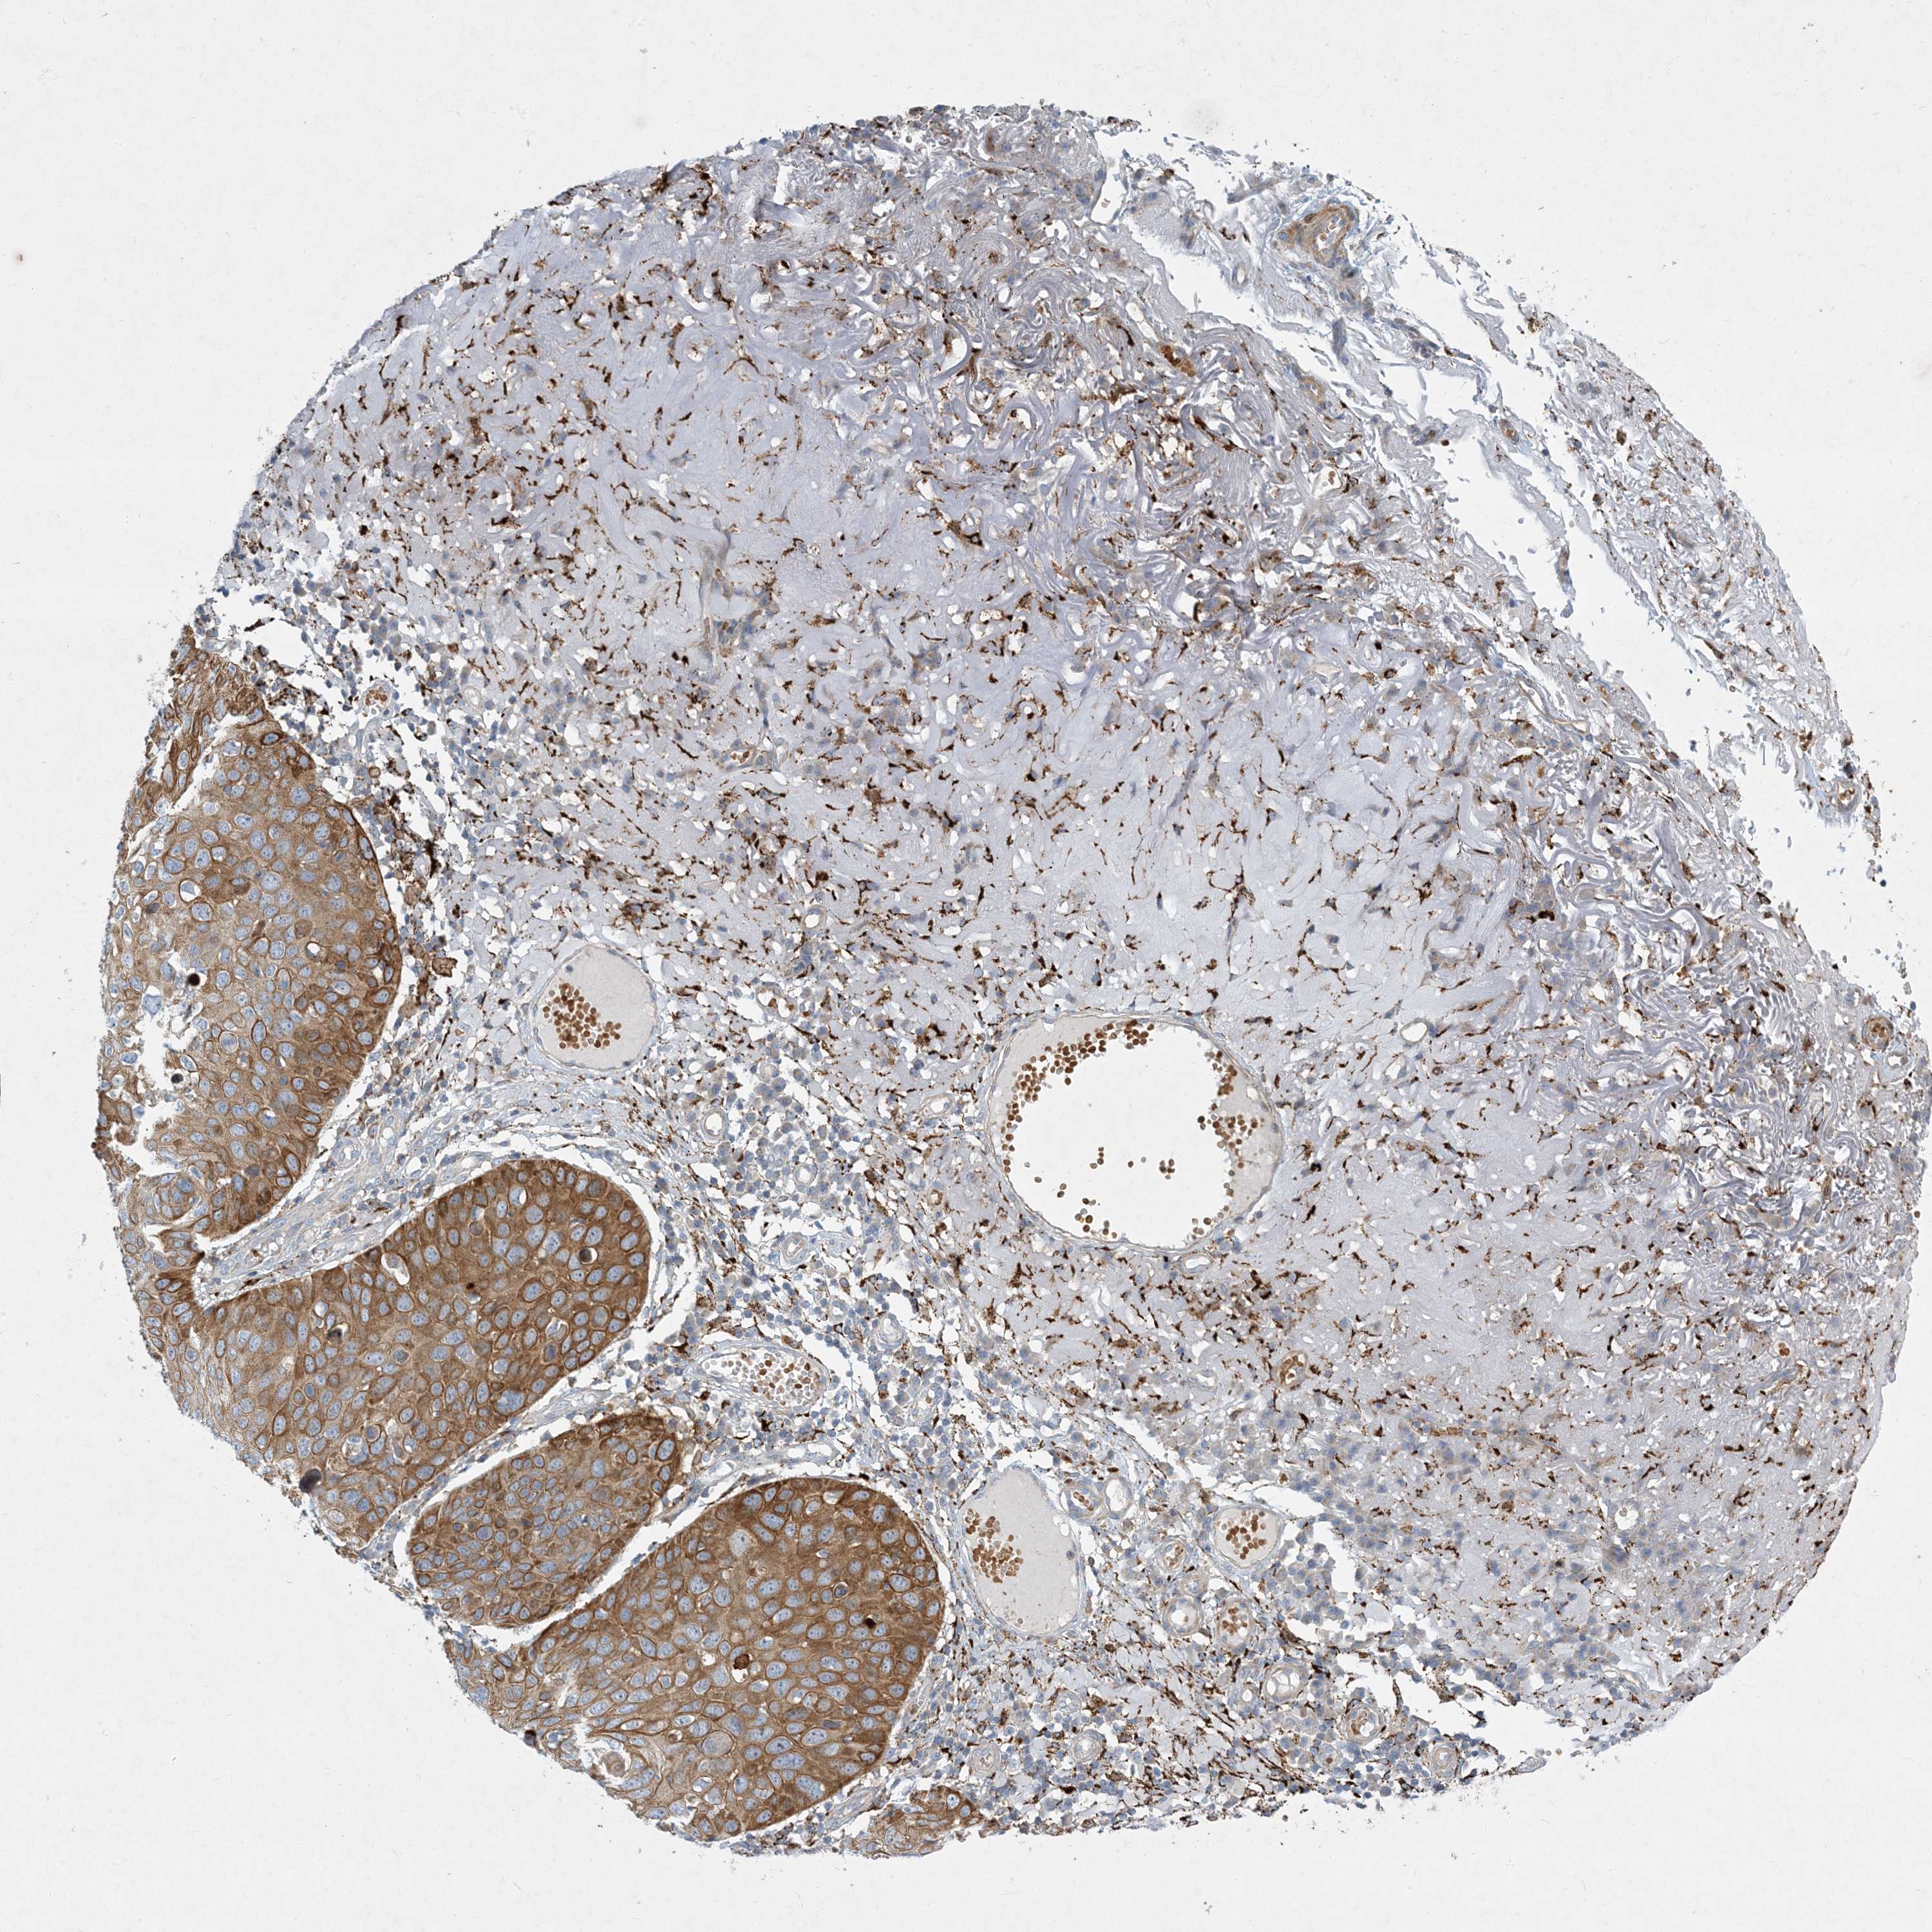

Basal cell and squamous cell cancer

SKIN CANCER - Protein expressioni

A mouse-over function shows sample information and annotation data. Click on an image to view it in a full screen mode. Samples can be filtered based on level of antibody staining by selecting one or several of the following categories: high, medium, low and not detected. The assay and annotation is described here.

Each image is clickable and will lead to virtual microscopy that enables deeper exploration of all samples and also displays staining intensity scores, fraction scores and subcellular localization as well as patient and tissue information for each sample.

Antibody HPA029143

Squamous cell carcinoma, metastatic, NOS